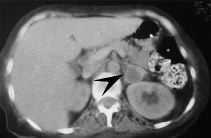

Una paciente de 46años, con historia de hipertensión arterial, acude alhospital por dolor subxifoideo opresivo, náuseas y disneaprogresiva, que hace necesaria su intubación yconexión a ventilación mecánica. Elelectrocardiograma (ECG) de ingreso muestra ritmo sinusal y datosde hipertrofia ventricular sin otros datos de interés, y uncorazón ecocardiográficamente normal. Durante losprimeros días presenta tendencia a la hipertensión.Evoluciona posteriormente con inestabilidad hemodinámica,por lo que ante la sospecha de un feocromocitoma se determinanmetanefrinas y ácido vanil mandélico en orina de 24horas, con valores respectivos de 10 mg (r.n. hasta 1 mg/24 h) y 18mg (r.n. hasta 5 mg/ 24 h). En la tomografía axialcomputarizada (TAC) abdominal (fig. 1) se observa unatumoración suprarrenal izquierda de 3 cm compatible confeocromocitoma; y la gammagrafía con131metaiodobencilguanidina (fig. 2) detecta un foco deactividad aumentada en área craneomedial delriñón izquierdo. La paciente fue tratada con alfabetabloqueantes y adrenalectomía evolucionandofavorablemente.